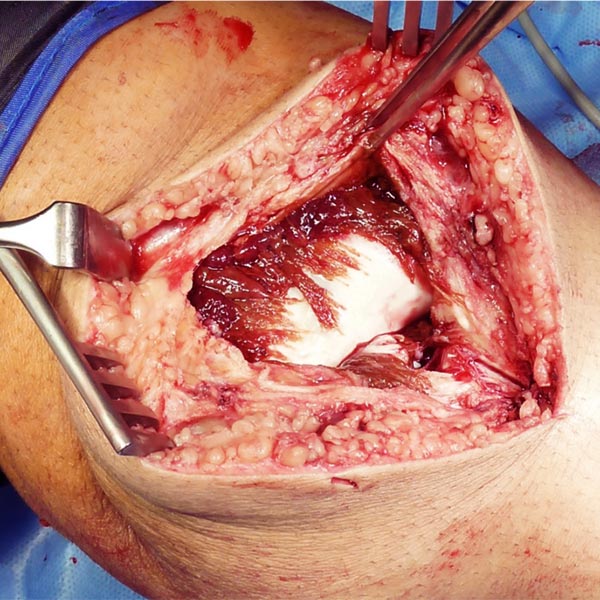

Intraoperative image after removal of the synovium and the intra-articular venous malformation. Remnants of the venous malformation are still present above the anterior cruciate ligament. Extensive cartilage damage at the lateral femoral condyle.

The venous malformation was then completely removed, and the anterior cruciate ligament is now fully visible and exposed. The cartilage damage was covered and treated by a so-called extracellular matrix.